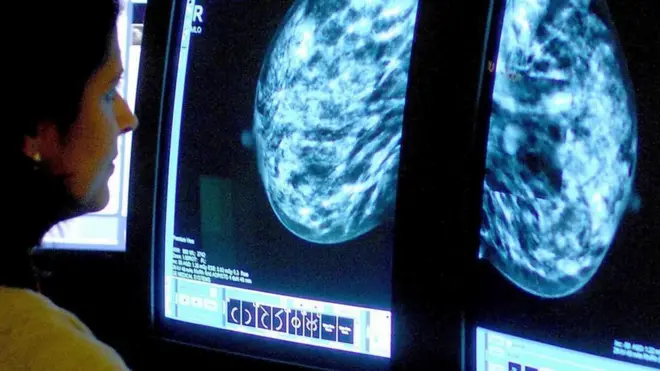

बबी शाक्यलाई पहिलो पटक स्तन क्यान्सर हुँदा उनका जुम्ल्याहा बच्चाहरू आमाको दूध खाने उमेरका थिए।

त्यतिबेला २७ वर्षीया उनले देब्रे स्तनको शल्यक्रिया गराउनुपर्यो।